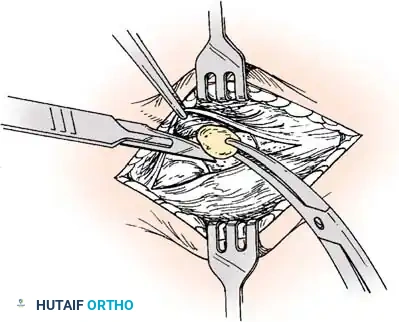

2. Transposition and Advancement of the PTT

-

Ossicle Excision: Using sharp dissection, meticulously shell the accessory navicular out from the substance of the posterior tibial tendon. If transposition of the tendon is planned, attempt to leave a microscopic sliver of bone within the tendon to enhance subsequent bone-to-tendon healing.

-

Navicular Resection: Resect the medial prominence of the main navicular so that it is flush with the medial border of the first cuneiform. This is typically achieved using an osteotome, followed by a rongeur and rasp to smooth the cortical edges.

-

Tendon Advancement: Suture the PTT to the apex of the medial longitudinal arch. This can be achieved by utilizing local periosteum and ligamentous tissue to secure the transposed tendon slip, or by passing heavy non-absorbable sutures through drill holes placed in the center of the navicular and tying them dorsally.

- Biomechanical Reduction: Try to advance this slip of tendon while the talonavicular joint is anatomically reduced. Reestablish the medial longitudinal arch by holding the midfoot and forefoot in a cavovarus position during knot tying.